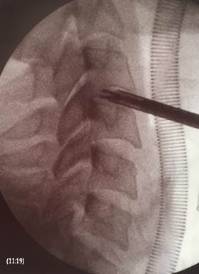

Imatge intraoperativa fluoroscòpica en perfil de la columna

cervical. Cal observar la pinça endoscòpica realitzant una

descompressió del disc intervertebral.